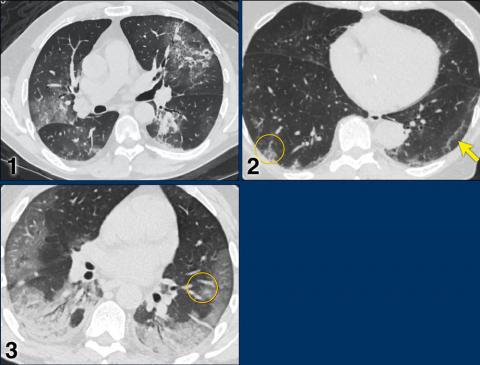

CO-RADS _____ (High - Suspicious for COVID-19)

CO-RADS _____ (very high level of suspicion for pulmonary involvement by COVID-19 based on typical CT findings)